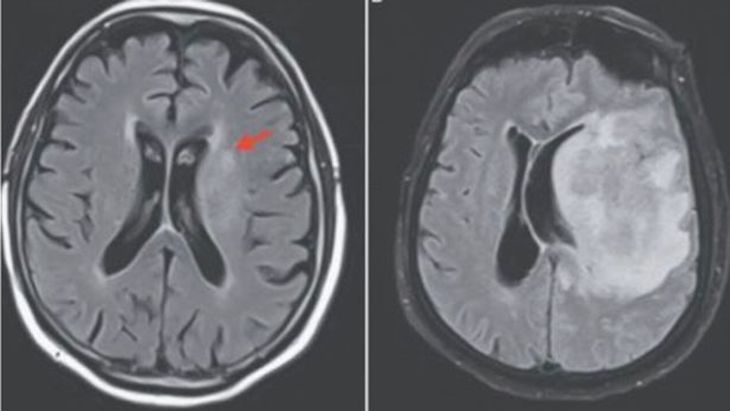

Правую сторону тела пожилого мужчины парализовало. Врачи сразу же поняли, что он умирает. Тогда они провели повторное обследование, но на этот раз решили просканировать его мозг.

Снимок показал, что правая часть мозга американца превратилась в кашу. По словам специалистов, причиной стали свободноживущие амёбы, которые жили в почве растения.